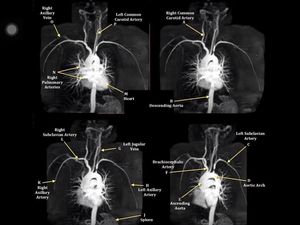

CE MRA of the subclavian arteries

Mri

Mra

Ce Mra